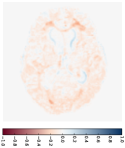

Apart from the subject-specific image prediction, our model can also estimate a group trajectory by predicting forward and backward image sequences for the atlas (the mean image) built for that group. Figure 6 demonstrates the mean trajectory estimated for the demented group. We first estimate the mean image using the unbiased atlas building algorithm (Joshi et al., 2004). This atlas is our baseline input, and we predict vector momenta forward to generate future image scans. By using the negative vector momenta, we shoot the atlas backward and generate previous image scans. From the predicted images within 25 years (every three years shown in Fig. 6), we can recognize the brain changes, in particular, the enlarging ventricle over the years. The deformation maps shown in the second row are generated starting from the atlas in the middle. Therefore, they show the expanding grids in the forward sub-sequence and the compressed grids in the backward sub-sequence.